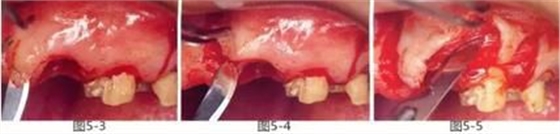

圖5-3~5

切開(kāi)牙齦至膜齦聯(lián)合處,形成半厚瓣。此時(shí)要注意手術(shù)刀的切入角度,謹(jǐn)慎操作以防造成齦瓣穿孔。